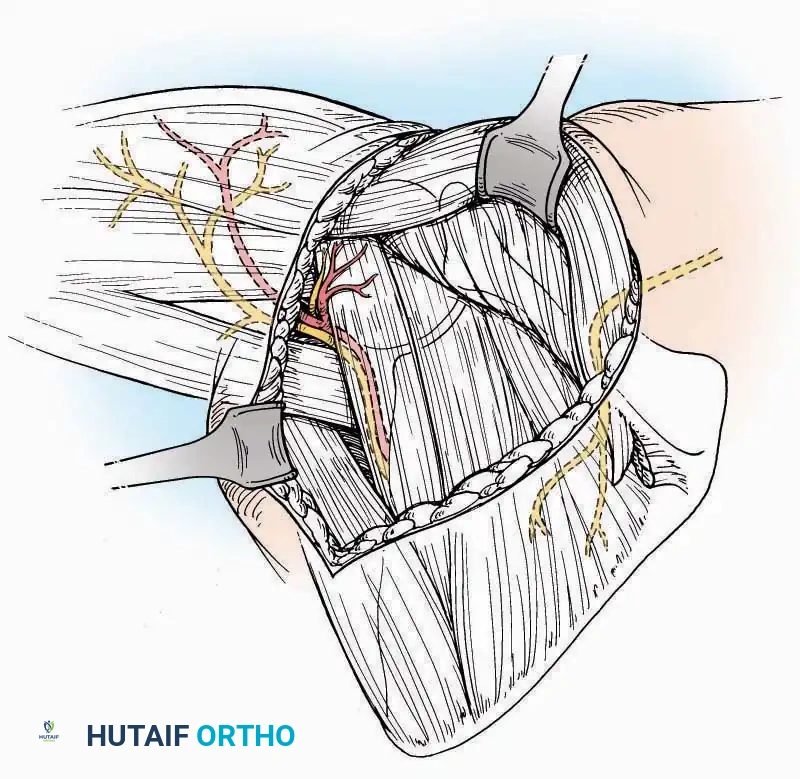

Anterolateral Approach

The anterolateral approach is widely considered the "universal incision" for the foot and ankle. It provides unparalleled access to the ankle joint, the talus, and the majority of the tarsal articulations, while safely avoiding the major anterior neurovascular bundle. The only tarsal joints inaccessible via this route are the naviculocuneiform joints (specifically the medial and intermediate).

Indications: Total talectomy, triple arthrodesis, ankle arthrodesis, and open reduction of complex talar neck fractures.

Surgical Technique:

* Incision: Begin over the anterolateral aspect of the leg, medial to the fibula and 5 cm proximal to the ankle joint line. Carry it distally over the joint, crossing the anterolateral aspect of the talar body and the calcaneocuboid joint, terminating at the base of the fourth metatarsal.

* Superficial Dissection: Incise the superficial fascia and the superior and inferior extensor retinacula down to the periosteum of the tibia and the ankle joint capsule.

* Vascular Ligation: This trajectory usually requires the identification and ligation of the anterolateral malleolar and lateral tarsal arteries.

* Nerve Protection: Retract the skin edges carefully. Identify and protect the intermediate dorsal cutaneous branches of the superficial peroneal nerve (SPN), which frequently cross the distal aspect of this incision.

* Muscle Management: Identify the origin of the extensor digitorum brevis (EDB) muscle on the lateral calcaneus. Divide it in the direction of its fibers, or detach its origin entirely and reflect it distally to expose the subtalar and calcaneocuboid joints.

* Deep Exposure: Retract the extensor digitorum longus (EDL) tendons, the dorsalis pedis artery, and the deep peroneal nerve (DPN) medially. Incise the anterior ankle capsule to expose the tibiotalar joint.

* Tarsal Exposure: Expose the talonavicular joint by dissecting deep to the extensor tendons and incising its capsule transversely. Continue laterally through the capsule of the calcaneocuboid joint. By excising the fat pad within the sinus tarsi (lateral and inferior to the talar neck), the posterior facet of the subtalar joint is brought into direct view.